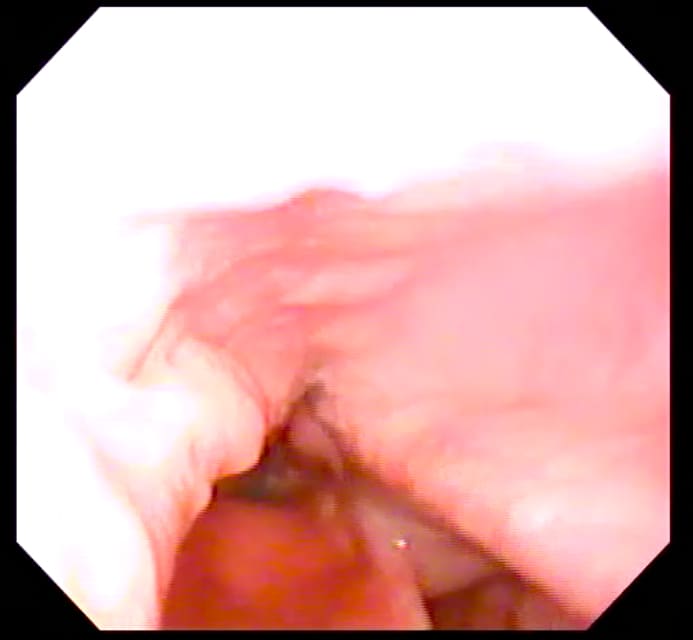

Larynx at Rest

Normal larynx, endoscopic view